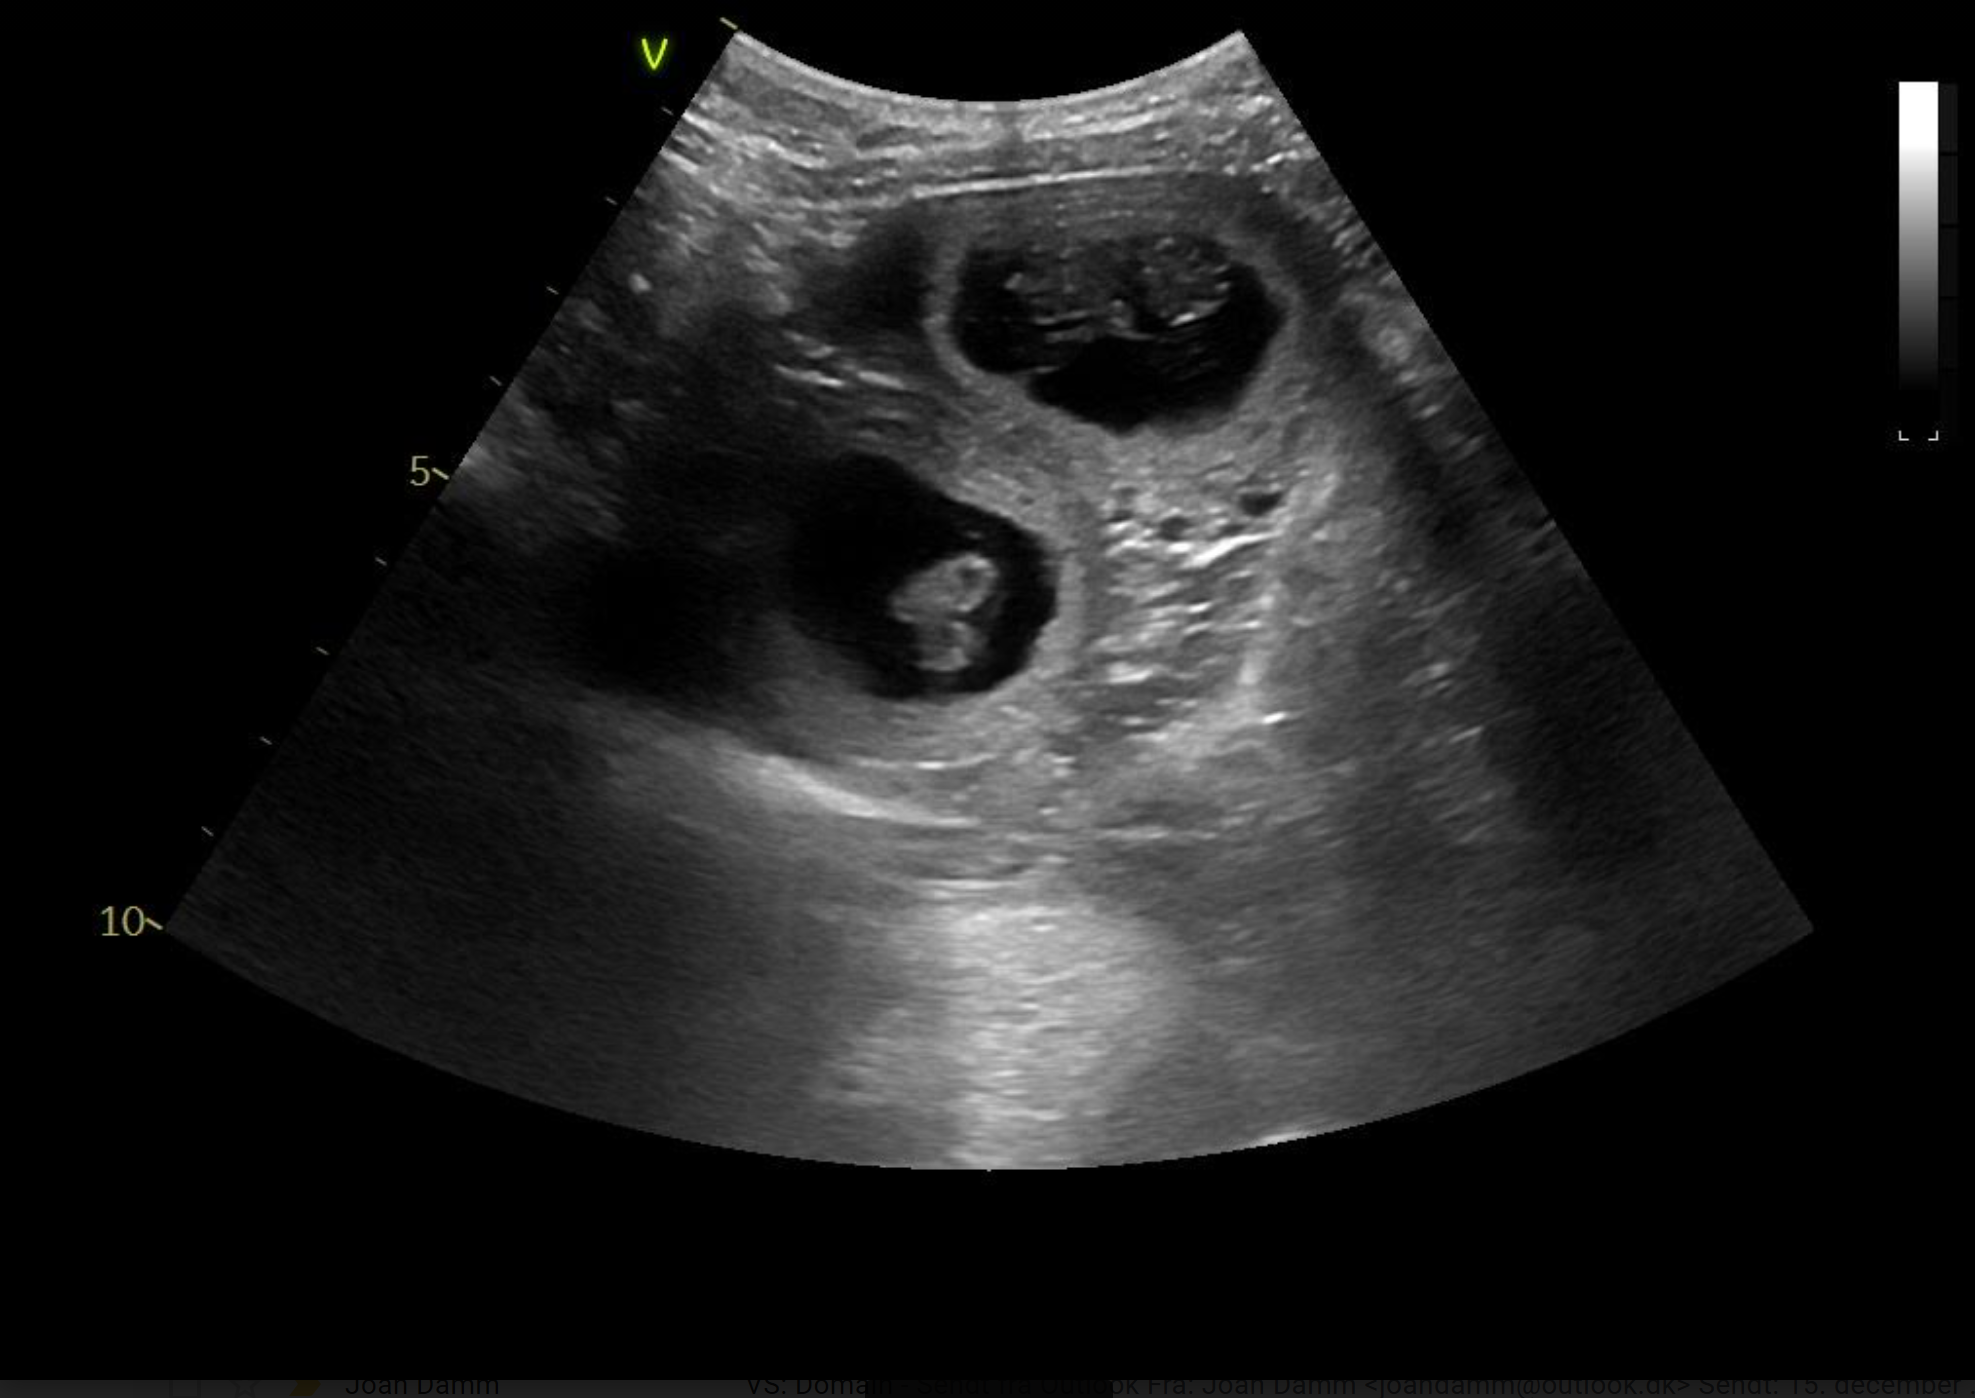

Tessa er scannet igen. Hvalpene er alle i live og har det godt. Deres hoveder er målt til 2 cm.

23.03.2021

Tessa er scannet drægtig. Hvalpene er sunde og er målt til 1,5 cm.